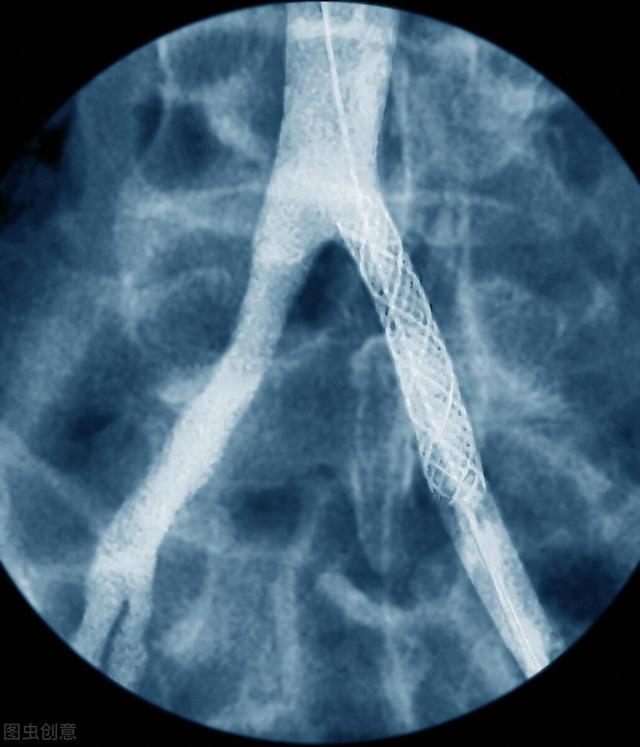

冠動脈造影検査で75%以上の冠動脈狭窄が検出された場合、医師は患者の年齢プロフィール、臨床症状、狭窄の程度などを考慮する。ステントの留置と留置本数が決定される。

(3) 冠状動脈性心臓病の治療:75%以上の前下行狭窄や突発性心筋梗塞のような重症の冠動脈疾患では、冠動脈造影と同時に拡張術やステント植え込み術などの必要な治療を行って、梗塞の治療や予防を行うことができる。

勿論、コンプレッサーを取り外した後でも適切な活動は可能ですが、術後1ヶ月間は、やはり実質的な運動は避け、回復を促進するために安静を主とする必要があります。手術中に冠動脈の狭窄の程度が50%以下であれば、冠動脈アテローム性動脈硬化症と見なされ、50%以上であれば冠動脈性心臓病と診断され、狭窄の程度が75%以上であれば、心臓ステント留置の適応の一つとなります。

ステント留置の適応は75%以上の冠動脈狭窄、頻回の狭心症発作、急性心筋梗塞などで、専門医の指導のもと、病態を総合的に判断して留置の可否を決定する必要がある。 ステント留置後は、生活習慣の改善と定期的な服薬に努め、病態の変化や定期的な経過観察に注意し、必要に応じてステントの再留置や冠動脈バイパス術を行い、病態の安定とコントロール、合併症の軽減を図る必要がある。必要であれば、ステントの再移植や冠動脈バイパス手術を行い、病状の安定とコントロール、合併症の軽減を図る。